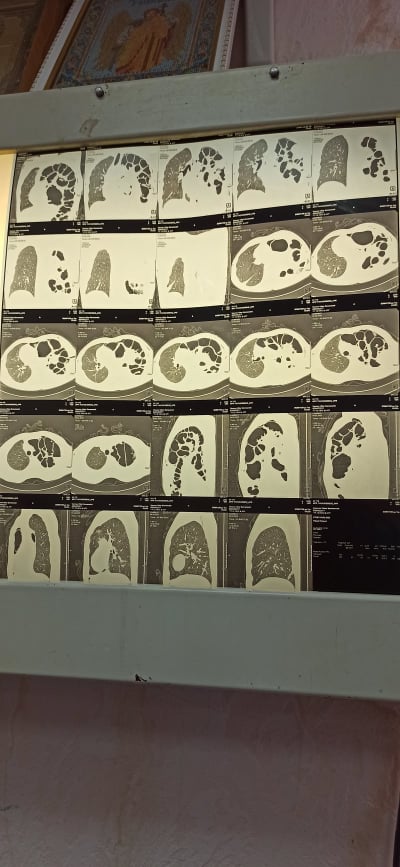

29 января, когда Белгород-Днестровский еще был припорошен снегом, муж Ольги Вороновой, Виктор, шел в гараж у себя во дворе. Мужчина поскользнулся и упал. В больнице, куда Виктор приехал, ему сделали КТ. Томография показала, что у мужчины сломано десятое ребро. Об этом журналисту информагентства «Юг.Today» рассказала жена Виктора, Ольга.

Сломанное ребро спровоцировало разрыв диафрагмы. Кишечник, желудок, селезенка и часть печени поднялись наверх. Виктора в срочном порядке прооперировали в Белгороде-Днестровском и направили в Одесскую областную больницу в очень тяжелом состоянии, где мужчине провели еще две сложнейшие операции.

Операция в областной больнице длилась 4 часа, ее проводили 4 хирурга. Операция прошла успешно, но у мужчины оказалась слабая диафрагма (последствия аварии, пережитой в молодости). Диафрагма порвалась, и Виктора прооперировали в третий раз.